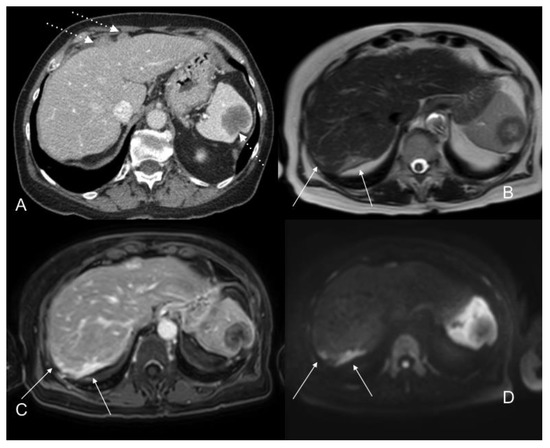

- Sugarbaker, P.H.; Sardi, A.; Brown, G.; Dromain, C.; Rousset, P.; Jelinek, J.S. Concerning CT features used to select patients for treatment of peritoneal metastases, a pictoral essay. Int. J. Hyperth. 2017, 33, 497–504. [Google Scholar] [CrossRef] [PubMed]

| Bowel obstruction or partial obstruction at more than one site |

| Mesentery drawn together by tumour (clumped bowel) |

| Tumour infiltrating between leaves of the small bowel mesentery |

| Tumour ≥ 5 cm in diameter in jejunal regions |

| Mesenteric or para-aortic lymphadenopathy |

| Hydroureter |

| Psoas muscle invasion |

| Pelvis sidewall invasion |

| Seminal vesicle invasion |

| Hepatoduodenal ligament infiltration and/or bile duct obstruction |

| Tumour ≥ 5 cm in diameter in gastrohepatic ligament or subpyloric space |

| Gastric outlet obstruction |